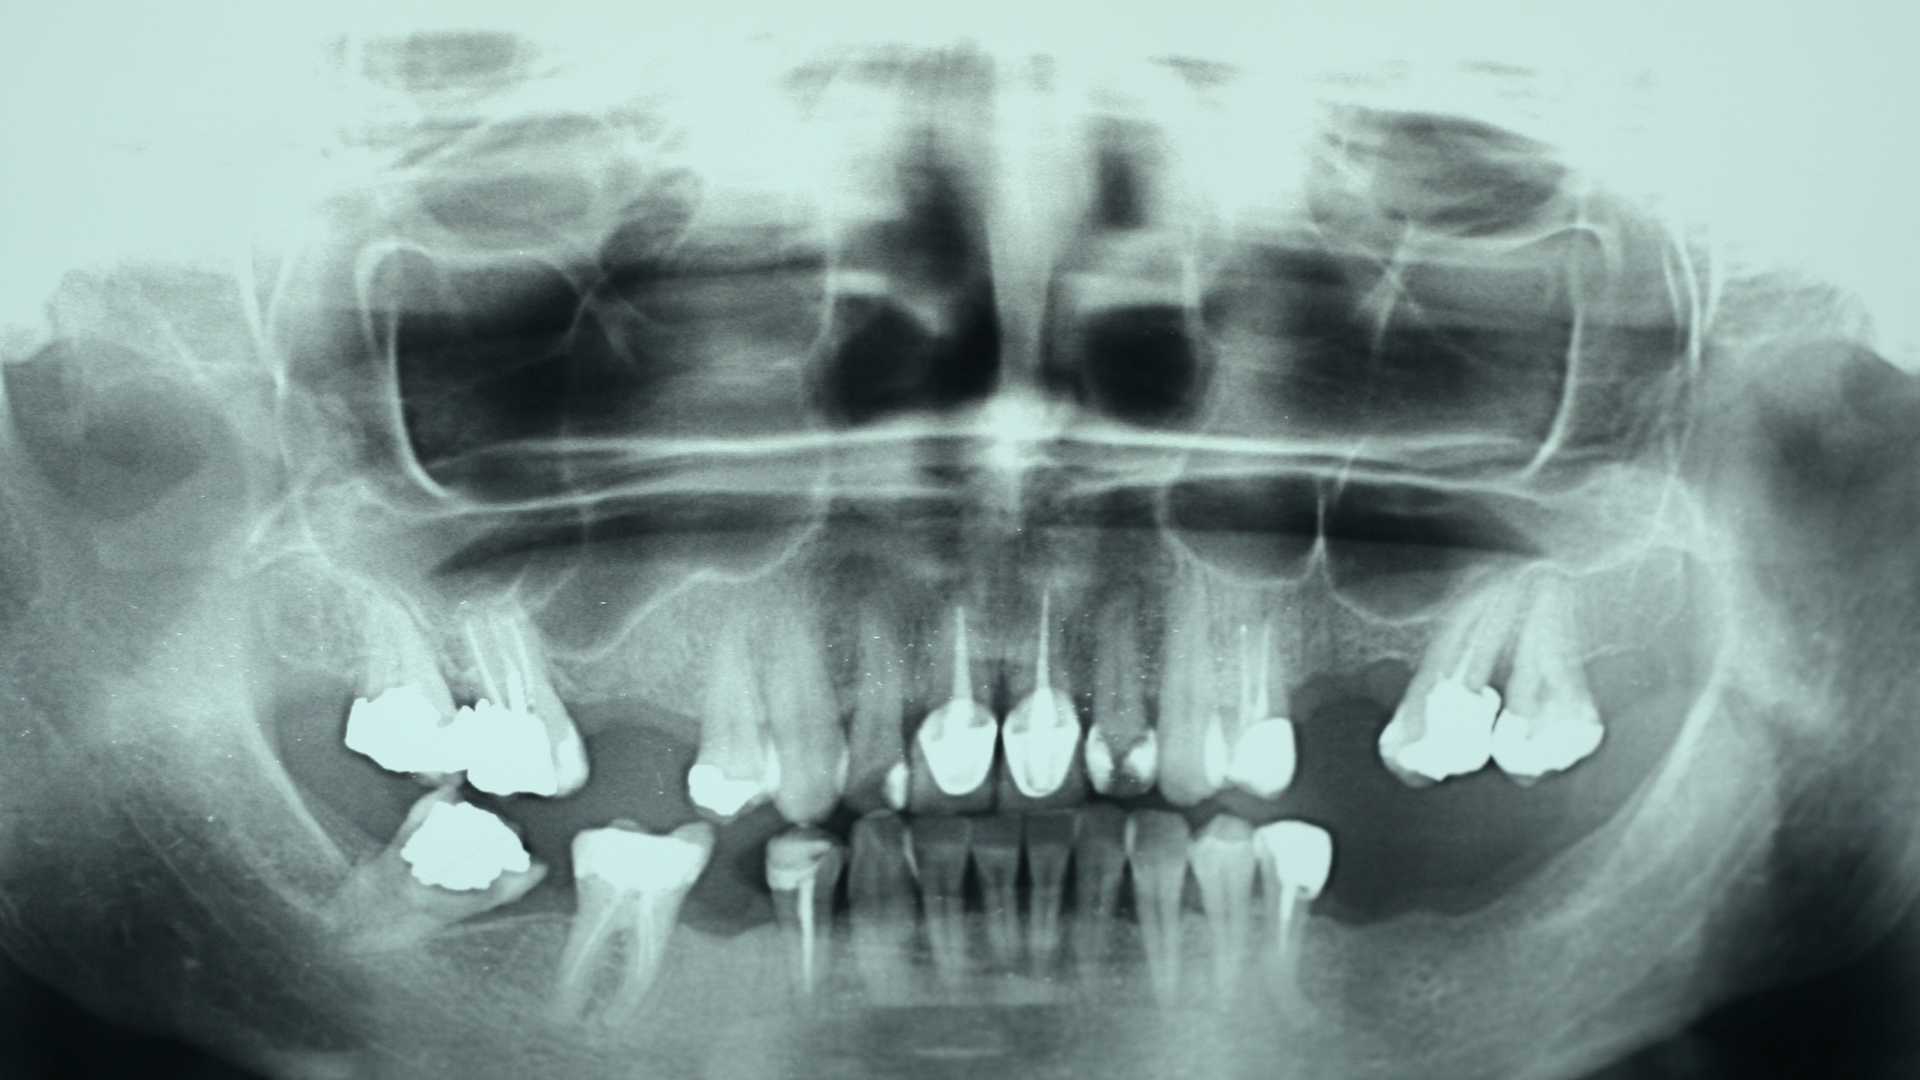

Chụp CT răng, phổ biến nhất là CT Cone Beam (CBCT), là kỹ thuật chẩn đoán hình ảnh sử dụng tia X với chùm tia hình nón để tạo ra hình ảnh ba chiều của răng, xương hàm, khớp thái dương - hàm và các cấu trúc lân cận. Khác với X-quang răng truyền thống chỉ cho hình ảnh hai chiều, CT răng cho phép quan sát không gian ba chiều với độ chính xác cao.

Nhờ khả năng tái tạo hình ảnh theo nhiều mặt cắt (ngang, dọc, chéo), CT răng giúp bác sĩ đánh giá rõ vị trí, hình dạng, kích thước tổn thương cũng như mối liên quan với các cấu trúc quan trọng như dây thần kinh răng dưới, xoang hàm hoặc xương ổ răng.

Phương pháp chụp CT răng không chỉ cho hình ảnh chi tiết mà còn giúp bác sĩ nhận diện nhiều bệnh lý quan trọng trong khoang miệng và xương hàm.